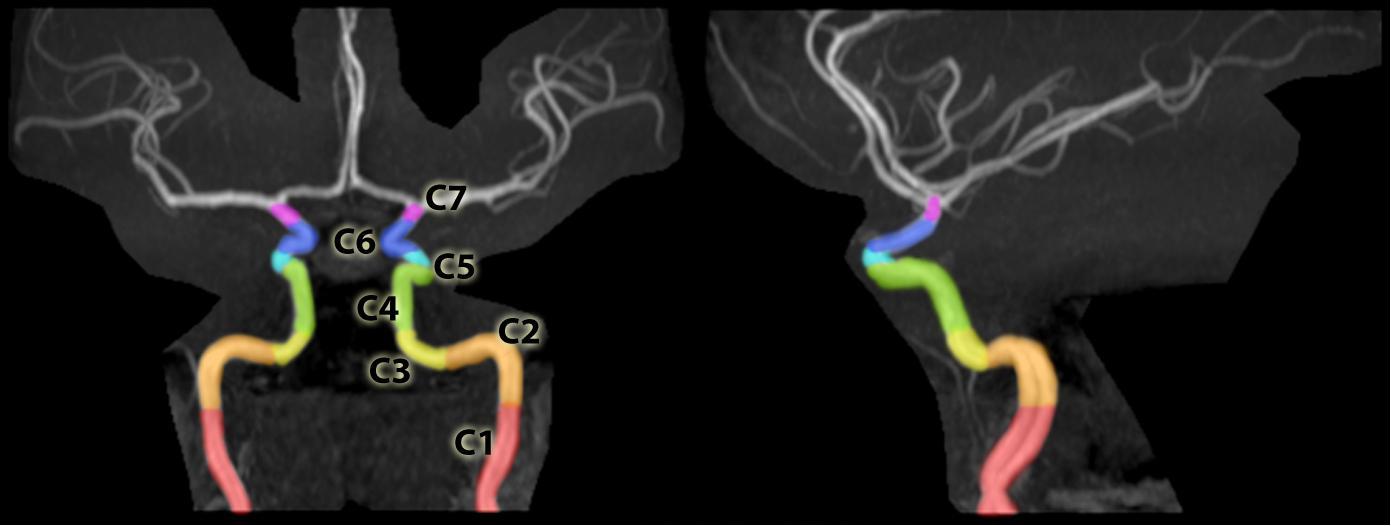

속목동맥은 뇌와 주변 구조에 혈액을 공급하는 중요한 동맥으로, 경부, 추체, 해면, 대뇌의 4부분으로 분류하거나, Bouthillier의 7개의 해부학적 분절(C1~C7) 분류 체계를 사용한다. 총경동맥에서 시작하여 경동맥관을 통해 두개골 내로 들어가며, 주요 가지로는 안동맥, 후교통동맥, 전맥락총동맥, 전대뇌동맥, 중대뇌동맥 등이 있다. 속목동맥의 상태는 도플러 초음파, CT 혈관 조영술 또는 PC-MRI를 통해 평가하며, 속목동맥 주위에는 교감 신경간에서 기원하는 경동맥총이 존재한다.

해부학 용어집(Terminologia Anatomica)에서는 1998년에 속목동맥을 경부, 추체, 해면, 대뇌의 4부분으로 나누었다.[3][4] 그러나 임상에서는 1996년 Bouthillier가 제시한 분류 체계를 따르는 것이 일반적이다.[5] 이 체계는 속목동맥을 C1부터 C7까지 7개의 분절로 나누어 설명한다. Bouthillier 분류법은 신경외과, 신경 방사선과, 신경과 의사들이 널리 사용하며, 각 분절은 해부학적 위치와 주변 구조를 기준으로 구분된다.

속목동맥의 분절은 다음과 같다.

C2와 C3는 추체부로, C6와 C7은 대뇌부로 통칭하기도 한다.